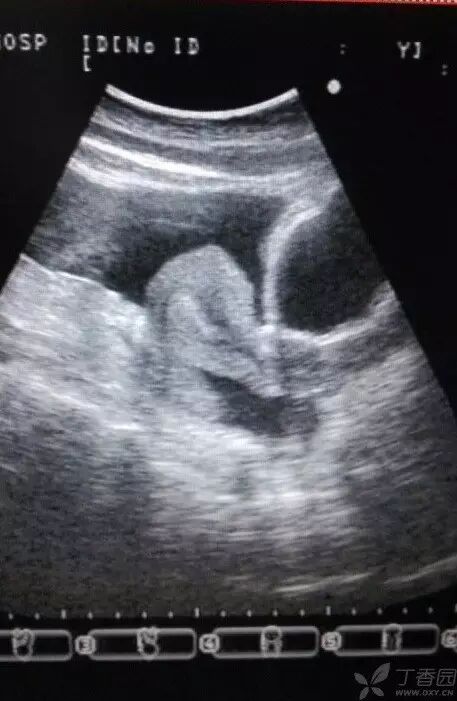

图1~3 显示子宫正常,盆腹腔可见两个相依的囊性肿物,其内见多条光带分隔,子宫被压在增大的卵巢下方